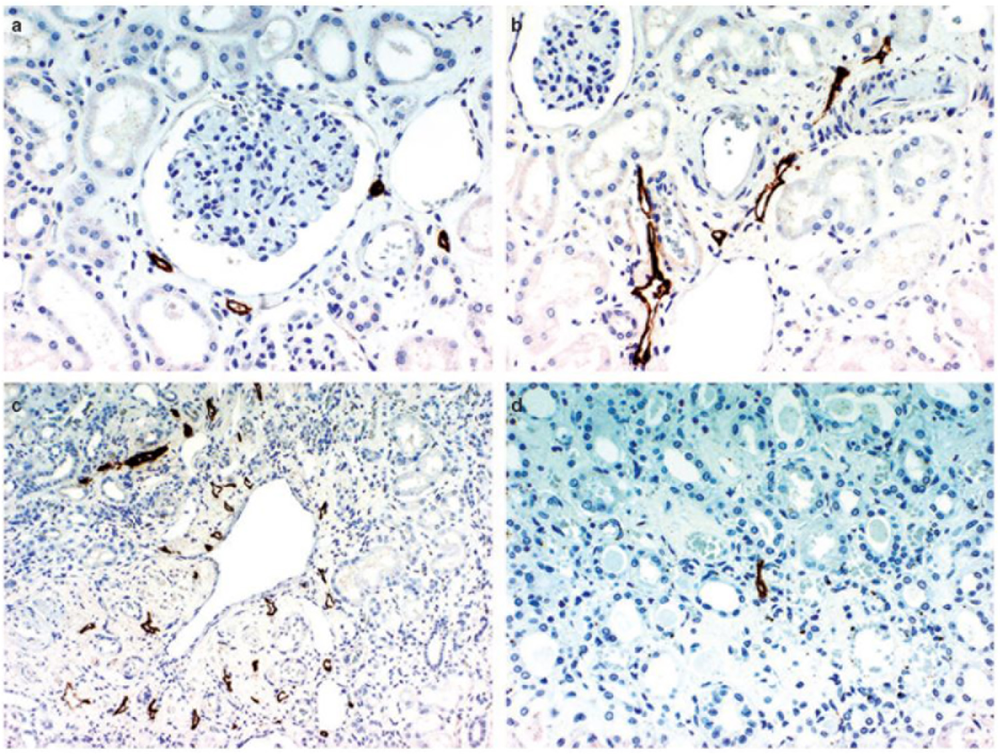

The basic mammalian renal lymphatic anatomy outlined above is the same as that found in humans (Figure 1). This was shown with microscopy at autopsy (Rawson, 1949) or using radiographic studies (Cuttino et al., 1989), and has been confirmed using LEC markers. Ishikawa et al. (2006), using podoplanin antibody (Figure 2), studied normal human kidney tissue obtained at autopsy, and confirmed that lymphatic vessels were most abundant in the interstitium surrounding interlobular, arcuate and interlobar arteries and veins.

Figure 2. D2-40 immunostaining of lymphatics in the normal kidney. (a) Lymphatic capillaries in the interstitium around the glomerulus, (b) lymphatics exhibiting a slit-like structure are distributed around the interlobular artery and vein in the cortex, (c) multiple lymphatic capillaries in the interstitium around a dilated interlobular vein, a few lymphatic capillaries are present just beneath the venous endothelium, (d) a lymphatic capillary is recognizable in the center of the figure showing a normal medulla. Reproduced with permission from Ishikawa et al. (2006).

Rawson (1949) mapped lymphatic distribution in a human kidney autopsy specimen. The specimen was from a patient with a gastric carcinoma that had metastasized in a retrograde manner into the renal lymphatics. This dilated the lymphatics and made them visible under the microscope. He concluded that renal lymphatics begin blindly in two areas; near Bowman’s capsule in the cortex, and beneath the mucosa of the papilla in the medulla. Those in the cortex drain down toward the arcuate vessels and those in the medulla drain up to meet them. Rawson’s findings have been controversial due to the presence of cancer in the renal lymphatics, and recent review articles have not relied on his work and instead have suggested, based on animal studies, that no lymphatic vessels are present in normal human renal medulla (Lee et al., 2011; Seeger et al., 2012). However, Ishikawa et al. (2006) found medullary lymphatics in normal human renal tissue in four out of ten cases (Figure 2), but only near the cortex, with none seen in the central area of the medulla.

Bell et al. (1968) found numerous small lymphatic vessels intimately associated with glomeruli, but none that penetrated into the glomerulus. These vessels either completely (horse) or partially (dog) surrounded Bowman’s capsule. Eliska (1984) was able to detect rare and very small lymphatics near tubules between interlobular arteries, and noted that lymphatics surrounding glomeruli become rarer with increasing distance from an interlobular artery. Ishikawa et al. (2006) confirmed that lymphatic capillaries sporadically surround the glomerulus in humans but do not penetrate it (Figure 2).